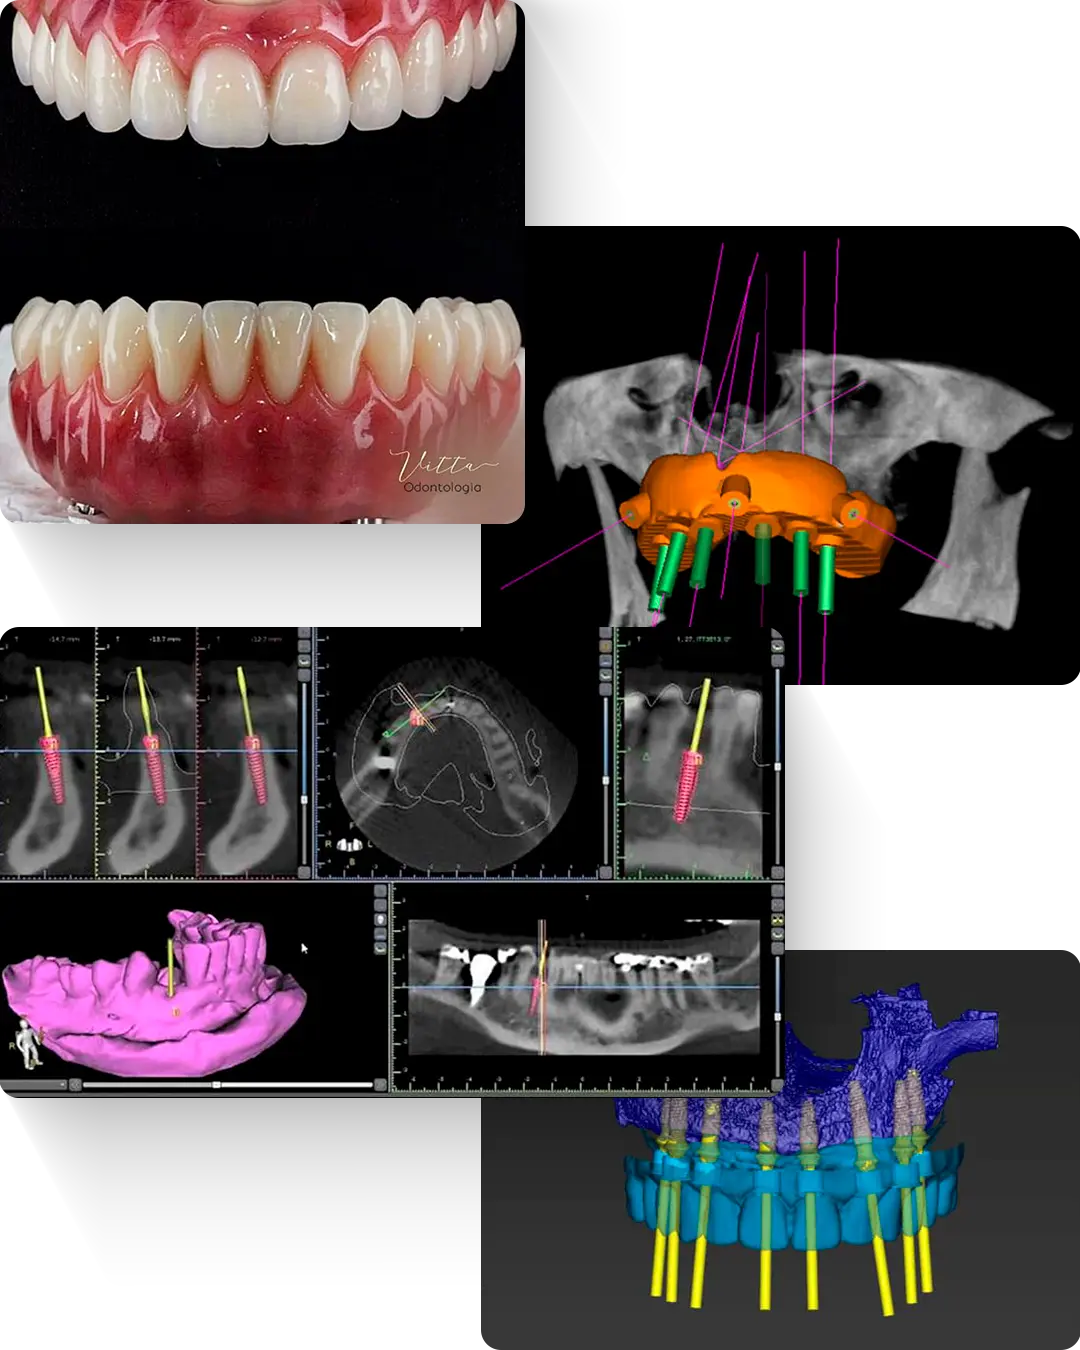

Os implantes dentários são pequenas estruturas de titânio colocadas no osso da boca para substituir a raiz do dente perdido.

Sobre esses implantes, instalamos próteses que funcionam como dentes: firmes, resistentes e esteticamente naturais.

Na Vitta Odontologia utilizamos cirurgia guiada digital, que permite:

O procedimento é realizado com cirurgia guiada, uma técnica minimamente invasiva que oferece mais conforto e segurança. Durante a cirurgia são instalados os implantes e, quando indicado, a prótese protocolo fixa pode ser colocada no mesmo dia.